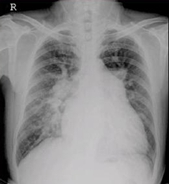

医学影像学的发展经历了三个阶段:X线的临床应用,放射学的形成,医学影像学的形成。

总体走向是建立现代医学影像学:从大体形态学向分子、生理、功能代谢基因成像过渡;从胶片采集、显示向数字采集电子传输发展;对比剂从一般性组织增强向组织疾病特异性增强发展;介入治疗,以及与内镜、微创治疗外科的融合、发展。

具体走向是:影像信息更加具有敏感性、直观性、特异性、早期性;图像分析由定性向定量发展:由显示诊断信息向提供手术路径方案发展;图像采集与显示:由二维模拟向三维全数字化发展;图像存储由胶片硬拷贝向软拷贝无胶片化,乃至图像传输网络化发展;从单一图像技术向综合图像技术发展。